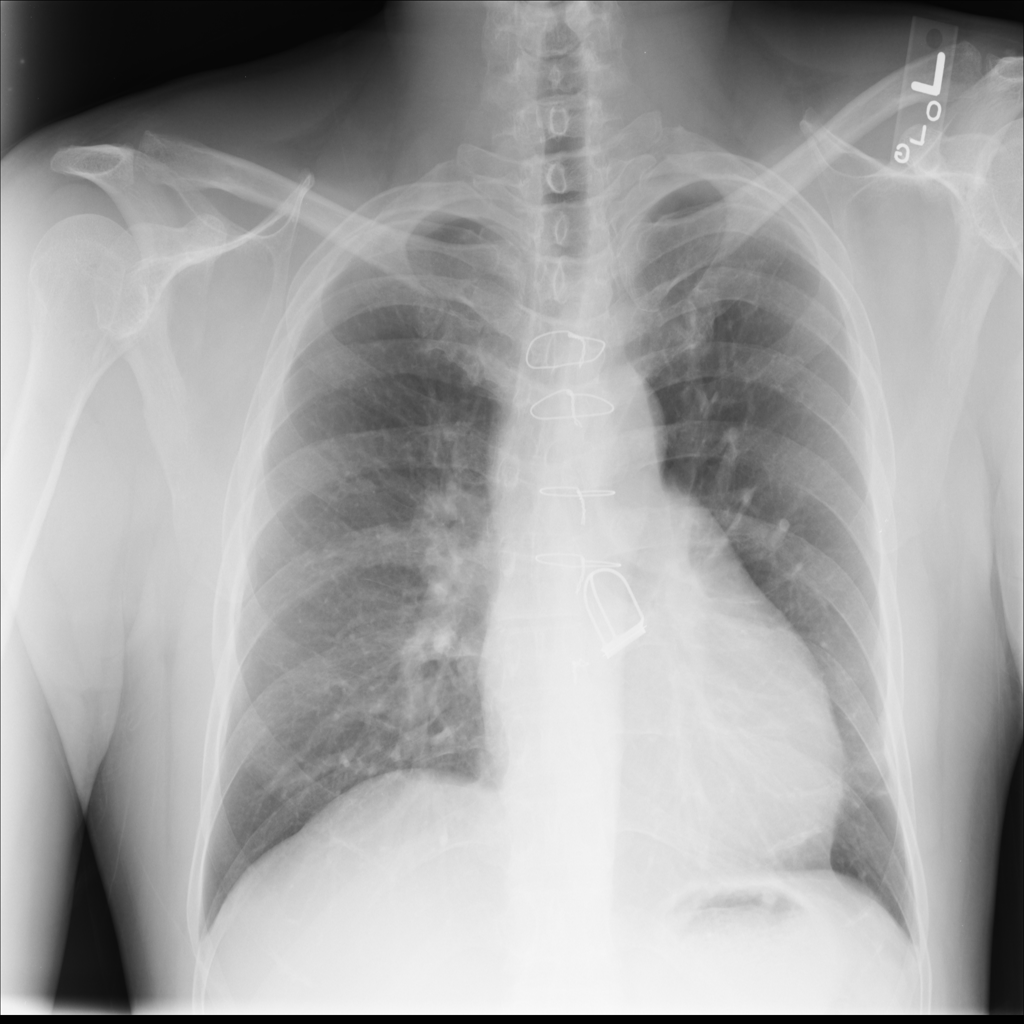

PAT-DB80 · IMG-000Atelectasis

PAT-DB80 · IMG-000

PA